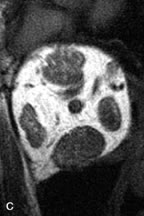

Lymphangiomas consist of ectatic vascular channels within a connective tissue stoma with varying degrees of lymphoid cellularity. On MRI, these tumors are typically poorly circumscribed, multicompartmental, and heterogeneous, often showing cystic dilations with fluid levels (Fig. 13). The signal characteristics within lymphangiomas vary considerably, reflecting cystic and solid components and the varying paramagnetic characteristics of blood at different stages of degradation.40–42 Acute hemorrhage appears hypointense on both T1- and T2-weighted formats. Methemoglobin present in subacute hemorrhage (3 to 14 days) leads to hyperintense signal on both T1- and T2-weighted images.41 A small percentage of lymphangiomas appear radiologically indistinct from orbital cavernous hemangiomas.43

Fig. 13. A. T1- and (B) T2-weighted MR scans demonstrate a moderately well-circumscribed intraconal mass enveloping the optic nerve. The lesion is hyperintense to vitreous on the T1-weighted scan. A fluid-fluid level (arrow) and patchy hypointense areas are seen within the mass on T2-weighted scan due to the presence of subacute blood products. C and D. Postcontrast fat-suppressed T1-weighted scans demonstrate no significant enhancement within the lesion, although there is minimal peripheral enhancement in surrounding orbital tissues.